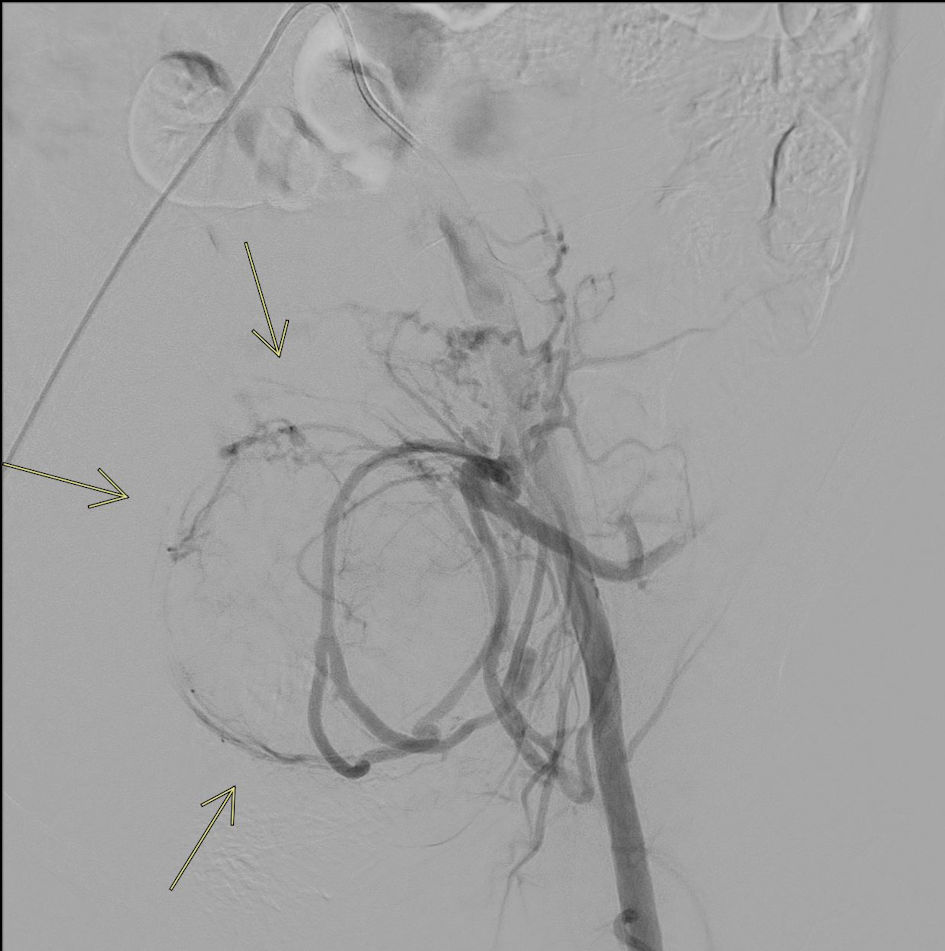

A magnetic resonance imaging (MRI) was subsequently ordered to further evaluate the extent of her uterine fibroids and anatomical variation due to uterine didelphys. MRI confirmed the presence of uterine didelphys with multiple large enhancing uterine fibroids distorting the endometrial cavity (Fig. 1). Fibroids were identified in both uteri, with the largest on the left measuring 14 × 11 × 11 cm and the largest on the right measuring 5.8 × 5.5 × 4.7 cm. Magnetic resonance angiography (MRA) demonstrated normal pelvic arterial anatomy with bilaterally enlarged uterine arteries, more prominent on the left. Prior to uterine artery fibroid embolization, MRA provides excellent visualization of the pelvic anatomy, assisting the interventionist in pre-procedural planning for the procedure (Fig. 2).

Figure 1. MRI of pelvis with intravenous contrast. Contrast-enhanced MRI of the pelvis demonstrates uterine didelphys with multiple large uterine fibroids, resulting in significant distortion of the endometrial cavity (arrows).